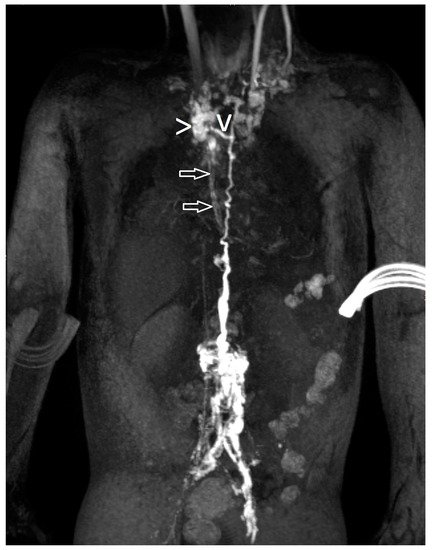

| 21 | 4 | increased signal mediastinum, hilum, lung le > ri | retrograde flow from TD with diffuse mediastinal and peribronchial perfusion | thoracic vertebrae 4–10 to left mediastinum | MCT diet, macitentan, alteplase inhalation, salbutamol, diuretics | glue embolization of TD | cast free after intervention (FU 1 a 4 m) tapering off sildenafil |

| 22 | 4 | increased signal (mediastinum), hilum/lung ri | retrograde lymphatic flow to mediastinum and lung parenchyma ri | from hilum to ri lung | fat reduced diet, sildenafil, alteplase/ fluticasone inhalation | selective glue embolization of 2 branches of TD | cast free after intervention (FU 4 a), cessation of fat-reduced diet, |

| 23 | 4 | increased signal mediastinum, hilum, lung ri > le | retrograde lymphatic flow towards lung parenchyma & mediastinum ri > le and peribronchial perfusion | fistula visualized | fat reduced diet, sildenafil, diuretics, alteplase inhalation, azithromycine | selective glue embolization of fistulas | cast free after intervention (FU 1 a 4 m) |

| 24 | 4 | increased signal at the mediastinum and hilum bilateral | retrograde lymphatic flow towards mediastinum and hilum bilaterally | no fistula visualized | diuretics salbutamol inhalation. Budesonide | TD decompression | cast free after OP, albumin normalized (FU 3 a 5 m) |